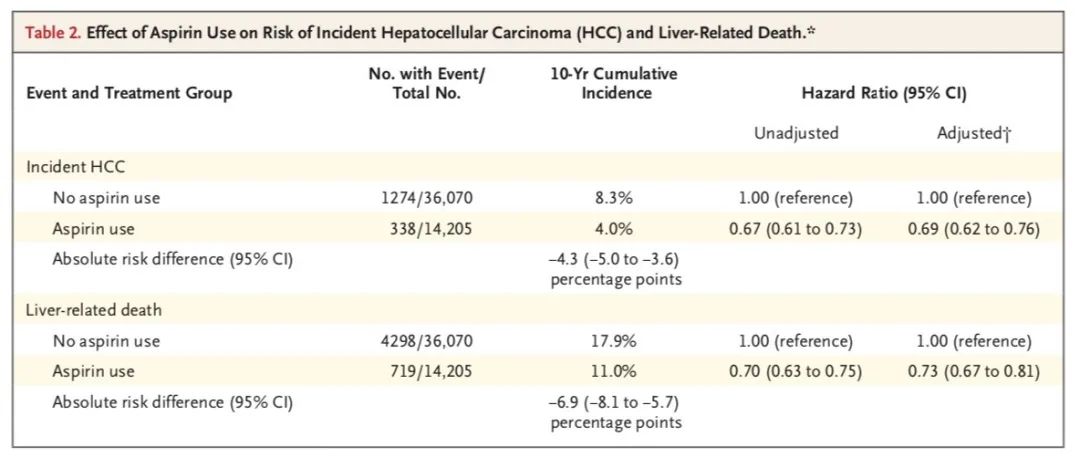

在中位时间长达7.9年的随访期间,有1612例肝细胞癌新发病例和5017例与肝病有关的死亡。尽管阿司匹林服用者普遍年纪更大,基础心血管状况更差,但肝细胞癌发病风险和肝病相关死亡风险都更低!

阿司匹林服用者的肝细胞癌估算累积发病率为4.0%,而非阿司匹林服用者中这一数字为8.3%。调整其他混杂影响因素后,服用阿司匹林的慢性病毒性肝炎人群,发生肝细胞癌的风险大幅降低了31%。

在服用者和非服用者中,10年肝病相关死亡率分别为11%和17.9%。调整其他混杂影响因素后,服用阿司匹林的慢性病毒性肝炎人群,死于肝脏问题的风险大幅降低27%。

在10年胃肠道出血风险方面,服用阿司匹林的影响不大。服用组和非服用组的发生率为7.8%和6.9%,没有显著差异。